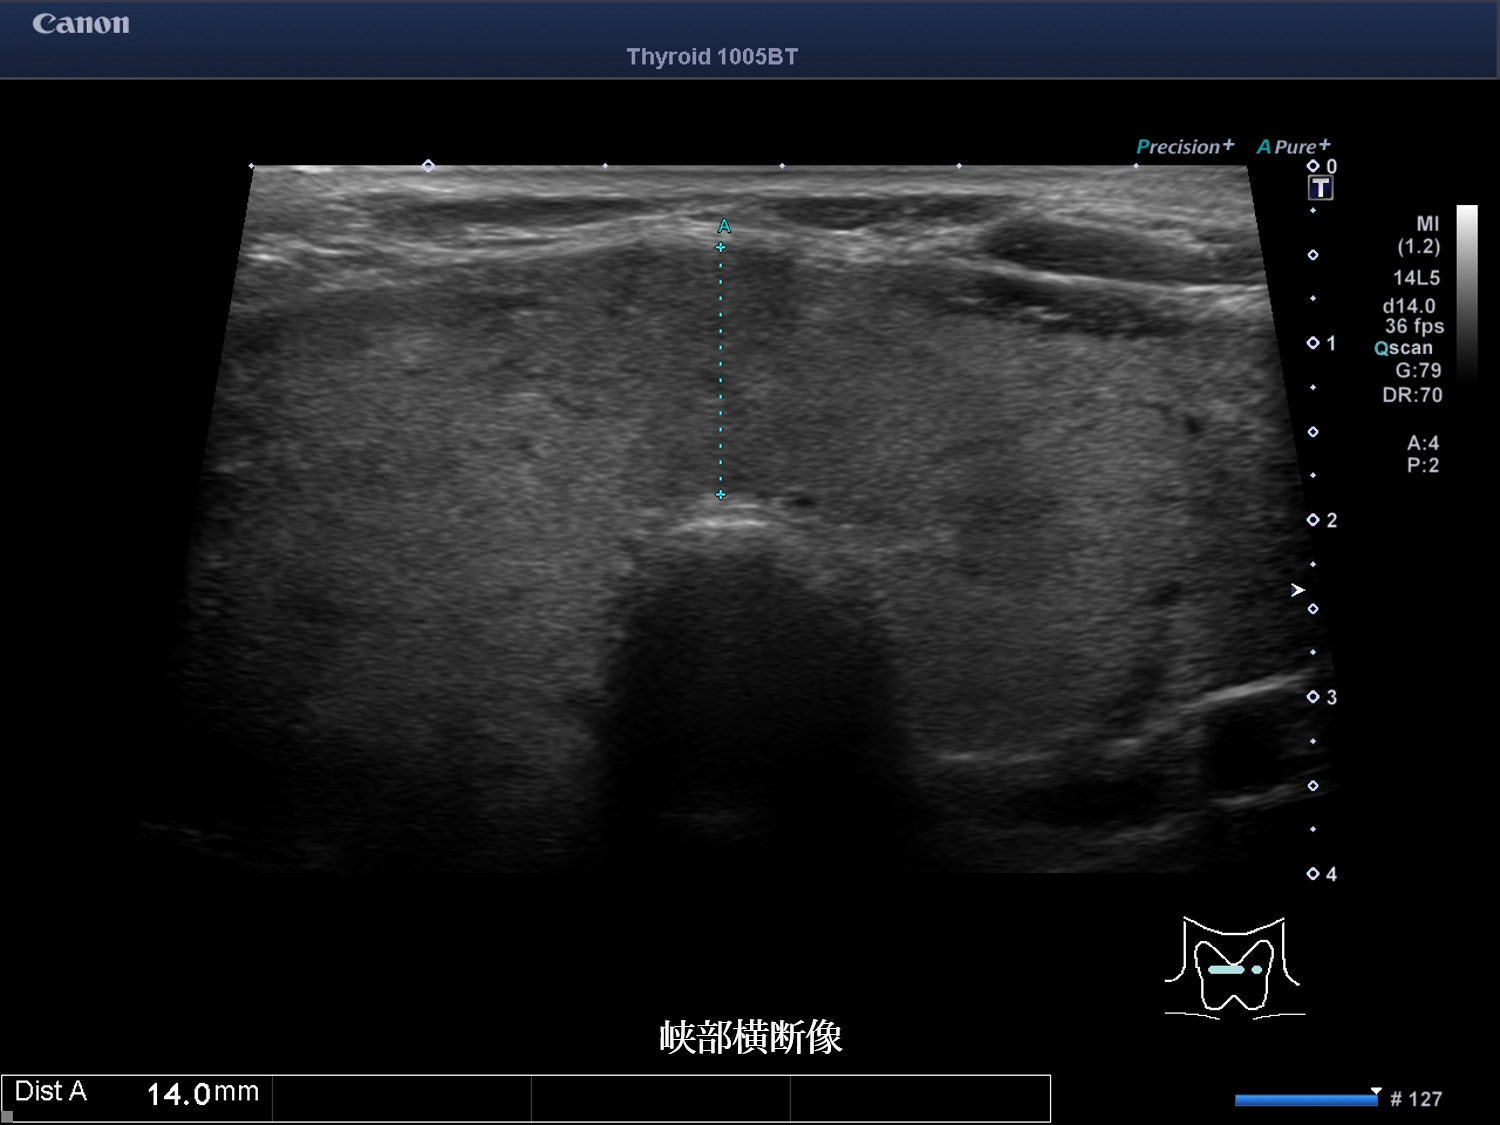

甲状腺超音波画像 画像1(No20-21_1)画像2(No20-21_2)画像3(No20-21_3)

誤っている超音波所見はどれか。

① 結節性病変は認めない

② びまん性に腫大している

③ 内部エコーは不均質である

④ 甲状腺内血流は増加している

⑤ 低エコー域内の血流低下を認める